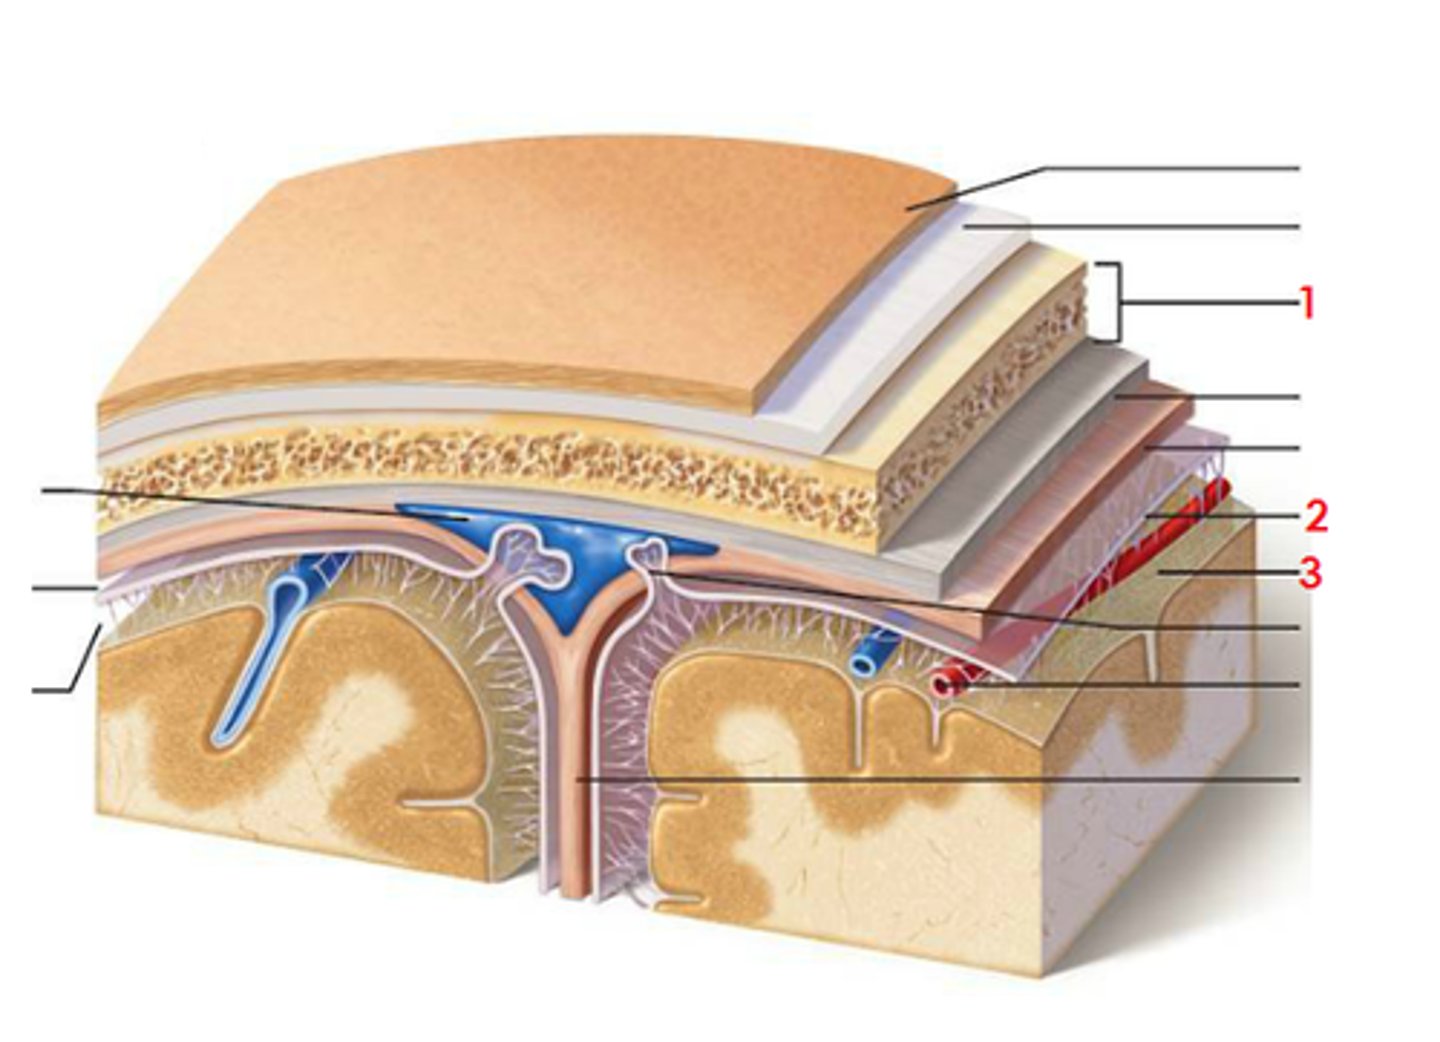

meninges

scalp, periosteium, then, 1st meningeal layer. Includes dura mater, arachnoid mater, and pia mater.

dura mater

2 layers. Periosteal layer (outer layer) and the meningeal layer - closest to next meningeal layer. This can create the dural venous sinus. right below 1 in this picture

arachnoid mater

meningeal layer on top. 2 in this picture

pia mater

sits directly on top of brain tissue. When CSF circulates, it circulates on top of brain tissue. If you try to tear pia mater away, you'll tear brain tissue. 3 in this picture